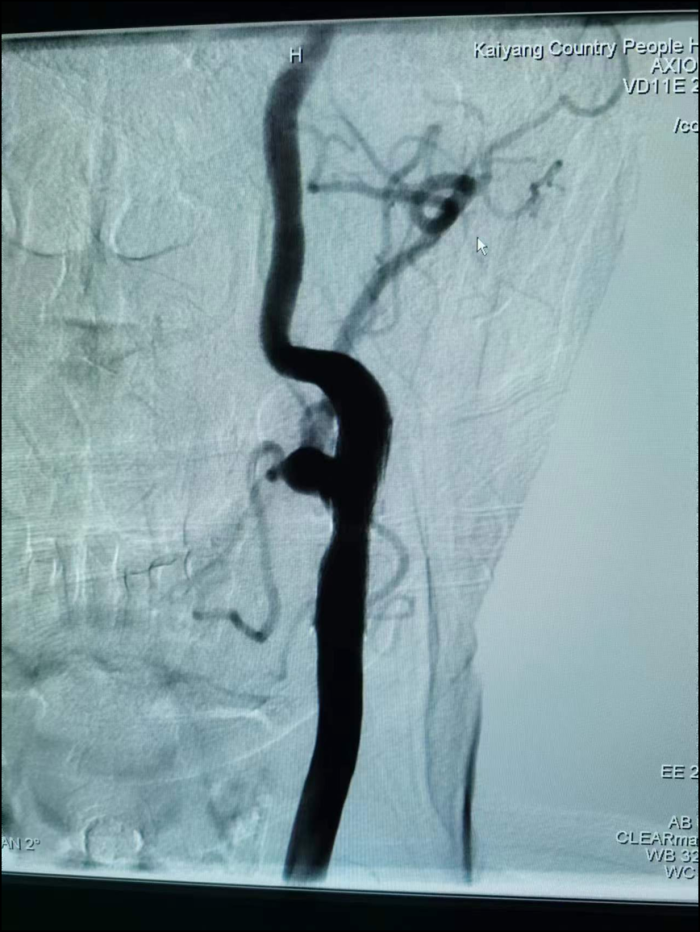

支架植入后

术后血管显影

手术顺利,术中患者生命征平稳,支架植入后造影见原狭窄处明显改善,患者原狭窄处发生闭塞风险降低,术后继续服用阿司匹林肠溶片、硫酸氢氯吡格雷片、阿托伐他汀钙片治疗,头昏症状明显改善出院。